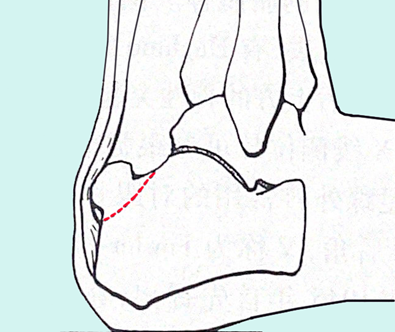

图11:Hugland结节切除示意图

图12:Hugland结节切除的角度和范围